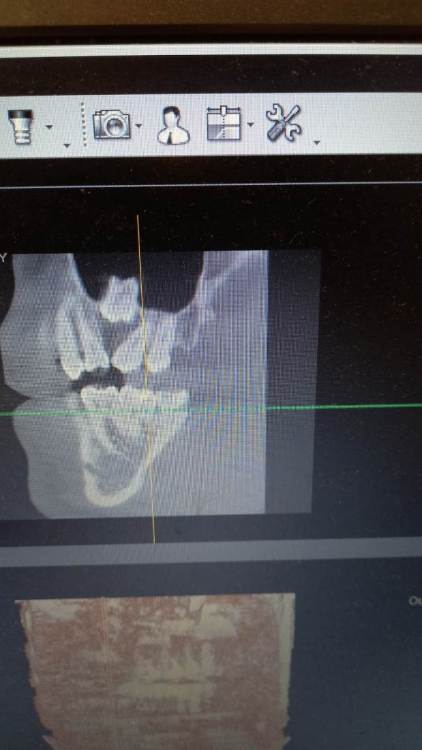

putinka17 Опубликовано 16 ноября, 2021 Поделиться Опубликовано 16 ноября, 2021 Сходил к врачу по поводу одной проблемы, он сказал что надо сделать КТ и тут появилась новая проблема, оказывается есть зуб который не вылез, ему места не хватило и он выпирает в пазухи. Я в шоке. Если учесть что он не вышел лет в 10 , то я ходил с ним 26 лет и никаких проблем не было. Врач говорит что его следовало бы удалить, но вопрос если он столько лет простоял пьчему бы ему дальше не стоять там. Ведь операция серьнзная если его удалять. Ссылка на комментарий